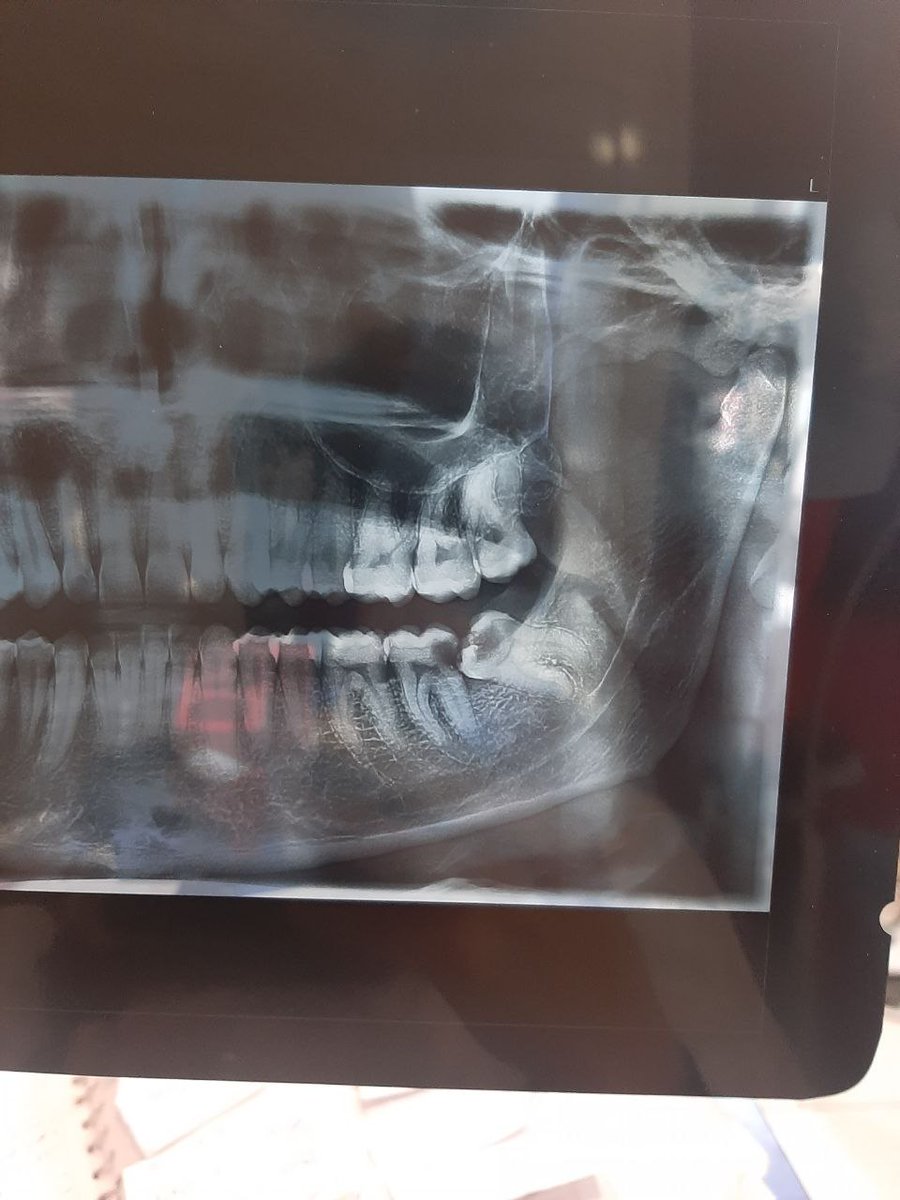

@arrrazz0 متخصص ارتو؟

باز خوبه خودش انجام داد

متخصص کلینیک ما همه بیماراشو دستیارش کار میکنه خودش فقط نگاه میکنه